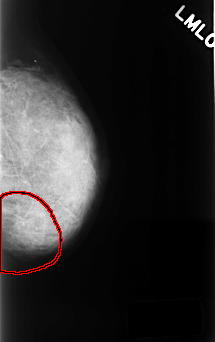

C_0400_1.LEFT_MLO

LEFT_MLO LINES 4440 PIXELS_PER_LINE 2784 BITS_PER_PIXEL 12 RESOLUTION 50 OVERLAY

FILE: C_0400_1.LEFT_MLO.OVERLAY

TOTAL_ABNORMALITIES 1

ABNORMALITY 1

LESION_TYPE CALCIFICATION TYPE PLEOMORPHIC DISTRIBUTION SEGMENTAL

ASSESSMENT 4

SUBTLETY 3

PATHOLOGY BENIGN

TOTAL_OUTLINES 1

BOUNDARY